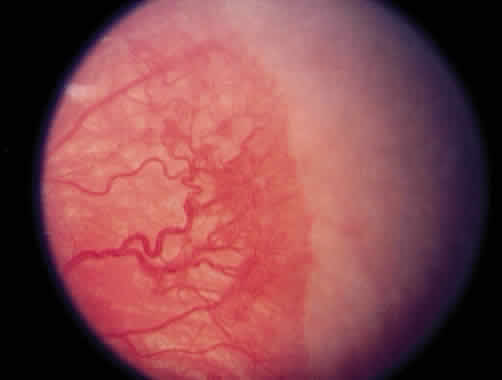

Laser is particularly useful in the management of zone I and posterior zone II disease. Most often, conjunctival incisions are necessary to get a cryotherapy probe posterior enough to treat zone I disease. This problem is obviated with laser delivery. Results of treatment of zone I disease in the Cryo-ROP Study are poor, whereas success rates of 80% to 90% have been reported in managing zone I disease with laser.71, 72, 73, 74, 75 Ridges in zone I or posterior zone II disease often are wider, with more defined vasculature than in zone II disease (Fig. 9). Zone I disease can be determined with a + 25 D lens. The disc is visualized at one rim of the lens, and avascular retina can be seen at the opposite rim when zone I disease is present (Fig. 10). A This occurs at a significant rate in the eyes of the smallest infants (500 g) with a gestation of 22 to 26 weeks. There may be an associated persistence of fetal vasculature (Fig. 11).

Fig. 11. Persistent fetal vessels in a premature infant of about 24 weeks' gestation.